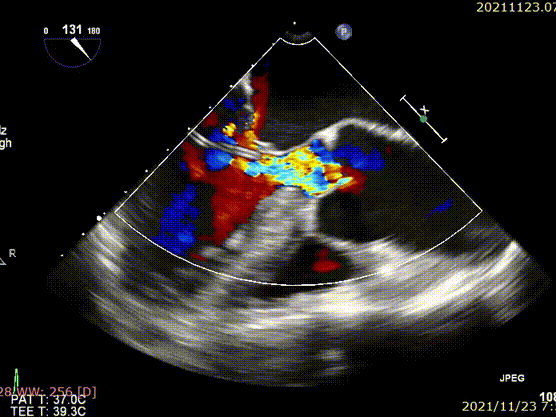

术前超声

术后超声

术后患者状态良好,CT评估未见异常,无瓣周漏,血流动力学良好。瓣膜植入后峰值流速0.82m/s,平均跨瓣压差1mmHg。